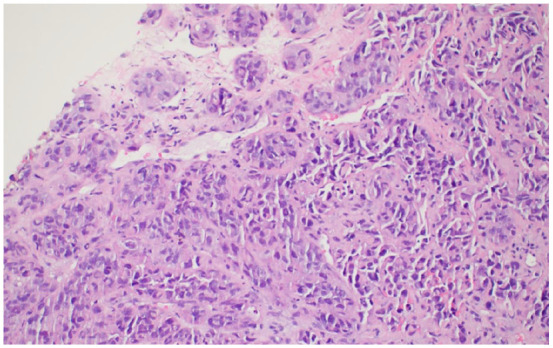

Metastatic melanoma to the breast is a rare phenomenon often mistaken for primary breast cancer due to overlapping clinical and imaging characteristics. We report the case of a 51-year-old woman with a history of melanoma resected 7 years earlier, presenting with severe left hip pain and a 6-month history of a right breast lump. Imaging revealed extensive metastatic disease, including lesions in the femoral head, breast, lung, adrenal gland, and thoracic spine. Pathologic examination of the hip lesion obtained during total arthroplasty, as well as biopsies of the breast and lung, confirmed metastatic melanoma. Histology revealed pleomorphic tumor cells with necrosis, while immunohistochemical analysis demonstrated SOX10 and S100 positivity, confirming the diagnosis. Genetic testing identified microsatellite stability with a tumor mutational burden of 16 mutations per mega base. This case shows the importance of thorough cancer histories and the use of immunohistochemical staining to distinguish metastatic melanoma from primary breast malignancies. Despite timely diagnosis and intervention, the patient's condition deteriorated rapidly, reflecting the aggressive nature of metastatic melanoma. This case highlights the need for vigilance in patients with a history of melanoma presenting with new breast masses to ensure accurate diagnosis and appropriate management.